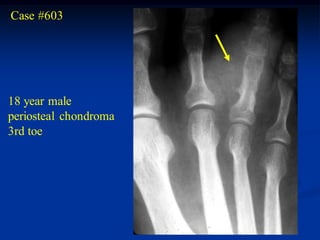

Case #603

18 year male

periosteal chondroma

3rd toe